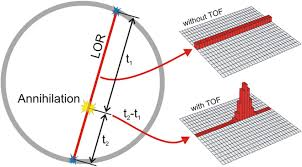

What is the new technology in PET that allows us to get an idea of where an annihilation event happened on the line of response?

Time of flight technology

What is time flight technology?

Where the new technology allows us to better determine where an annihilation event happened based on how soon (time) the photon hit the detector – i.e. it taking 0.5 seconds for the right side vs. 1.5 seconds for the left side → annihilation most likely happened more on the right

How does time flight technology affect how our images on PET turn out?

It decreases our need for having multiple line of responses – able to use shorter line of responses and get rid of all the bad and excess information that makes the images less clear – better able to focus on what we intend to image

How does time flight technology affect how we dose and image the patient in PET?

If we’re able to eliminate bad information using the new technology, we won’t need to overcome the bad information with good information – able to give less of a big dose and not need to image as long